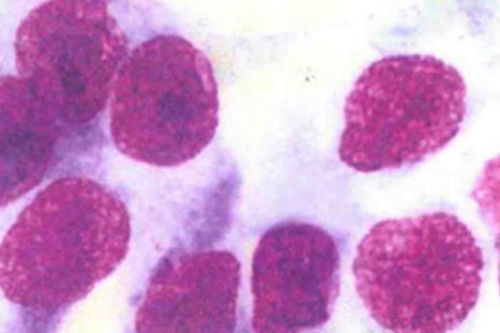

大便常规中的潜血试验是筛查结直肠癌的一个重要环节。潜血阳性的结果可能意味着肠道存在肿瘤性病变,如息肉、腺瘤或肠癌等。这一结果也可能受到其他疾病的影响,如痔疮、消化道溃疡等。在面对潜血阳性的结果时,我们需要保持冷静,结合其他检查手段进行综合分析。

为了更精准地筛查肠癌,我们推荐结合其他检查手段。粪便DNA检测通过基因突变分析,提高了早期癌症的检出率。而肠镜检查则是确诊肠癌的“金标准”,能够直接观察到肠道内的病变并取活检,为诊断提供有力依据。